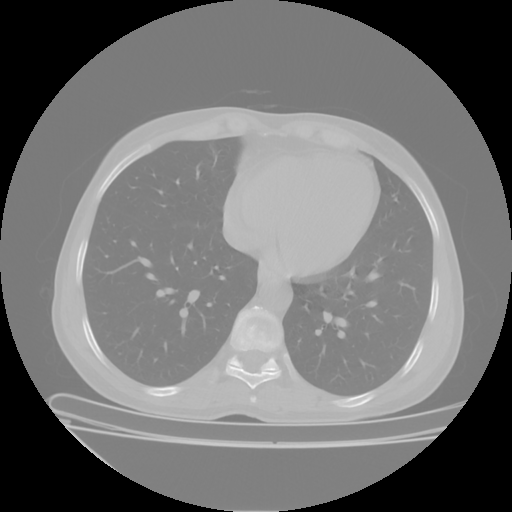

Original NATIVE CT scan (input)

Lung window (WL -600, WW 1500 β†’ Low βˆ’1350, High +150)

Reconstructed NATIVE CT scan (cycle consistency)

Original VENOUS CT scan

Generated VENOUS CT scan (A→B translation)